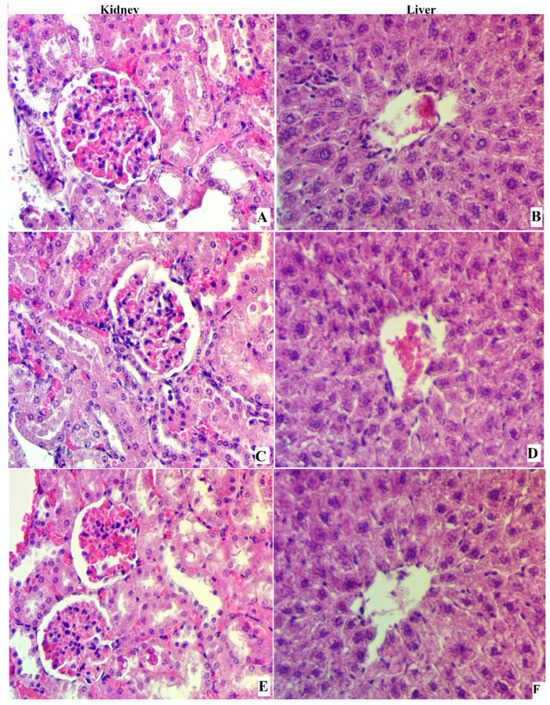

3.5. H&E Stain